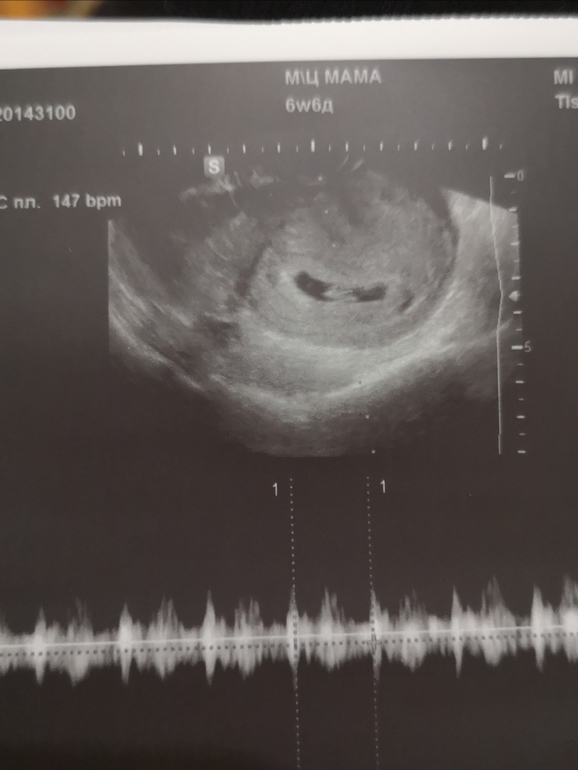

Завтра 7 недель. Была на узи. Расстроена

УЗИ, КТГ, доплерБыла сегодня на узи, в целом узистка сказала, что все хорошо, но я же читаю интернеты...

Желточный мешок больше, чем должен. Читала, что такое может говорить о генетических отклонениях.

Тонус, яичко очень сплюснуто.